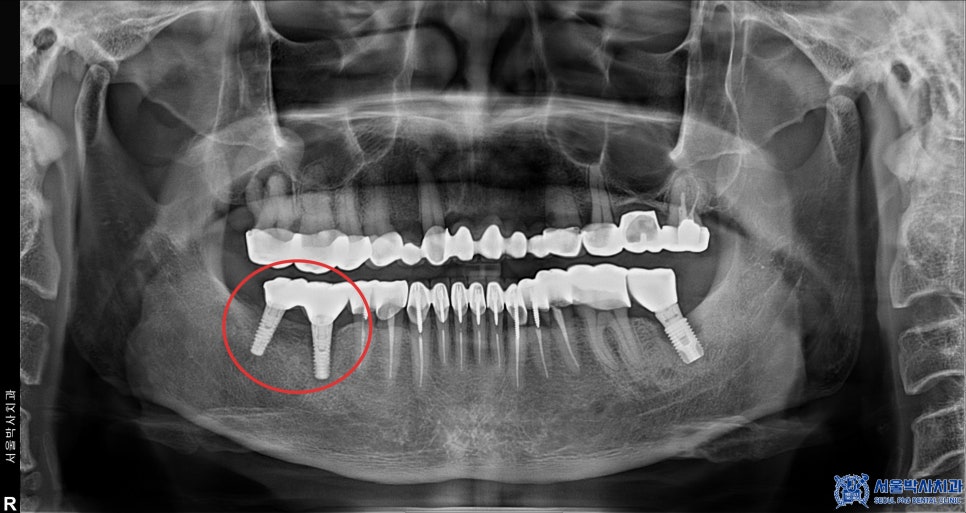

또한 위쪽 어금니 중 일부는

신경치료 후 크라운 치료로 충분히 유지할 수 있는

상태였기 때문에 발치를 진행하지 않고

기존 보철물을 제거한 후,

신경치료를 진행하여 새롭게

보철 치료를 시행하였습니다.

치료 마무리 후 사진입니다.

신흥동치과 신흥동치과

환자분께서는 임플란트 뿐만 아니라 신경치료 후

크라운 치료까지 진행하면서,

전체적인 구강 건강을 개선할 수 있었습니다.